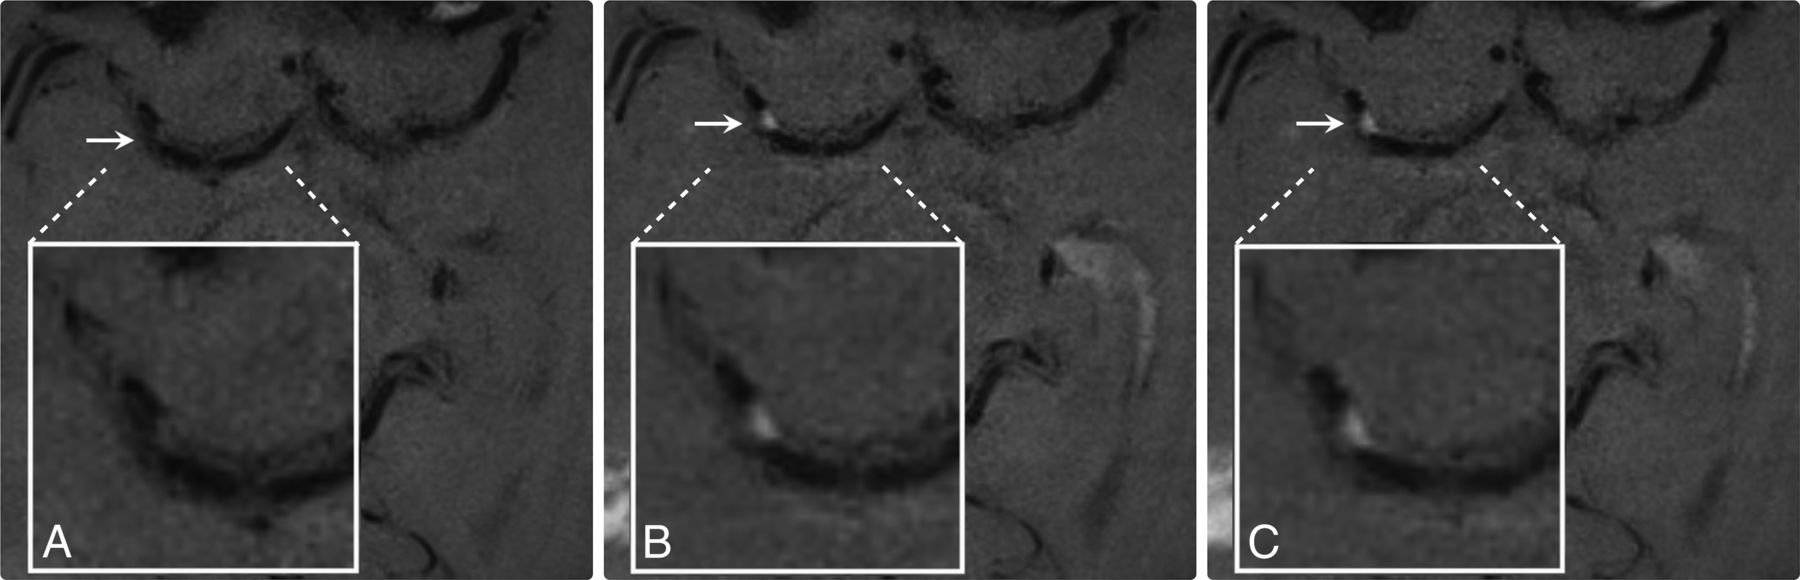

This series include precontrast (A), early postcontrast (B), and delayed postcontrast (C) T1 3D TSE sequences that demonstrates progressive enhancement of an ICAD plaque located in the right M1 segment of the right MCA in a patient presenting with an ischemic stroke in the corresponding vascular territory, suggestive of plaque instability. Note the excellent arterial blood flow (black-blood) suppression that allows focal identification of eccentric ICAD plaque enhancement (Plaques are annotated by a white arrow and magnified in box to demonstrate degree of enhancement in all of the above images).